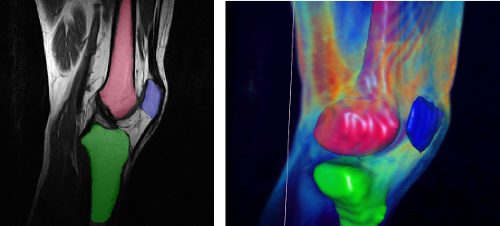

Halbautomatische Segmentierung der knöchernen Strukturen des Kniegelenks in MRT Aufnahmen

Zuverlässige Segmentierung ist eine der wichtigsten und zugleich komplexesten Aufgaben in der modernen Volumen Analyse. Besonders im Bereich der Medizin sind bildgebende Verfahren heute ein integraler Bestandteil des klinischen Alltags geworden, was zur Folge hat das ein hoher Prozentsatz der Arbeitszeit auf die Nachbearbeitung bzw. Strukturfindung aufgewendet werden muss. Hier setzen (teil-) automatisierte, modellbasierte Verfahren an. Eine prominente Klasse der modellbasierten Segmentierungsverfahren ist der "Deformable Model" Ansatz. Grundidee ist die Verwendung eines initiales Modells, üblicherweise durch ein 3D Netz repräsentiert, welches in einem iterativen Verfahren an die zu findende Kontur angepasst wird und sich in jedem Schritt ausbreitet oder schrumpft, vergleichbar mit einem Ballon in den (lokal) Luft hingepumpt oder abgelassen wird. Ziel dieser Arbeit ist es, unter Verwendung des am Welfenlab entwickelte YaDiV Deformable Model Framework (YDMF) angepasste Modelle für die knöchernen Strukturen im Bereich des menschlichen Kniegelenks (Patella, Femur, Tibia) zu entwickeln. Als Volumendaten werden MRT-Aufnahmen zum Einsatz kommen, was eine zusätzliche Herausforderung an das Modell darstellt, da die Differenzierung von knöchernen Strukturen durch Weichgewebe in MRT-Aufnahmen erschwert wird.

Als erster Schritt soll ein Modell für die Patella entwickelt werden, welches mit anatomischen Landmarken versehen wird und durch eine lokal und global angepassten Expansions- bzw. Erosionskraft die Strukturfindung ermöglicht. Das Modell soll mit einer geringen Auswahl an Datensätzten trainiert und anschließend durch die Anwendung in neuen Aufnahmen evaluiert werden. Die gewonnen Erkenntnisse sollen dann für die Modellierung der Femur bzw. Tibia Modelle genutzt werden, bei denen die zusätzliche Herausforderung besteht, das hier oft nur eine Teilabdeckung im Aufnahmebereich besteht. Betreuer: Karl-Ingo Friese November 2011